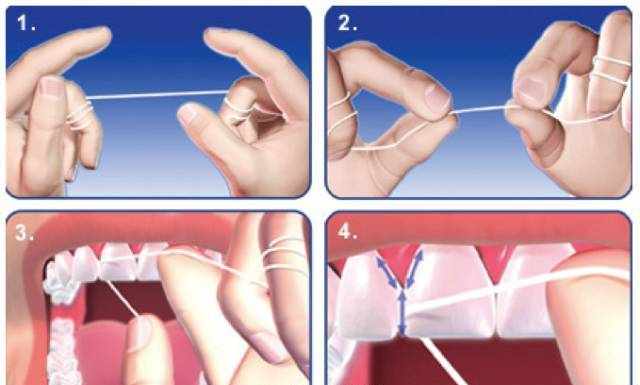

牙线

对于牙线的使用频率,从一次小范围的调查中可以发现,只有62%的人达到标准。

每天刷牙前或刷牙后至少使用一次牙线,不过要确保应用正确的牙线使用方法,这样才能发挥最佳功效,如果使用方法不正确,可能会对牙龈造成机械性损伤。

很多人使用牙线采用的是简单的前后拉锯的方法,然而这种方法无法充分清洁牙齿邻面和牙龈缘的部位。

正确的操作是将牙线弯曲成C形状,置于牙齿间隙和牙龈缘,上下移动牙线去除食物残渣。